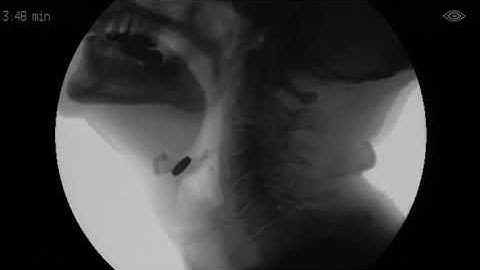

Why do Things Go Down the Wrong Way When Swallowing Sometimes (Aspiration)?